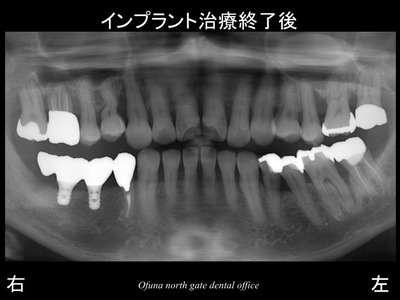

以下は治療終了後です。